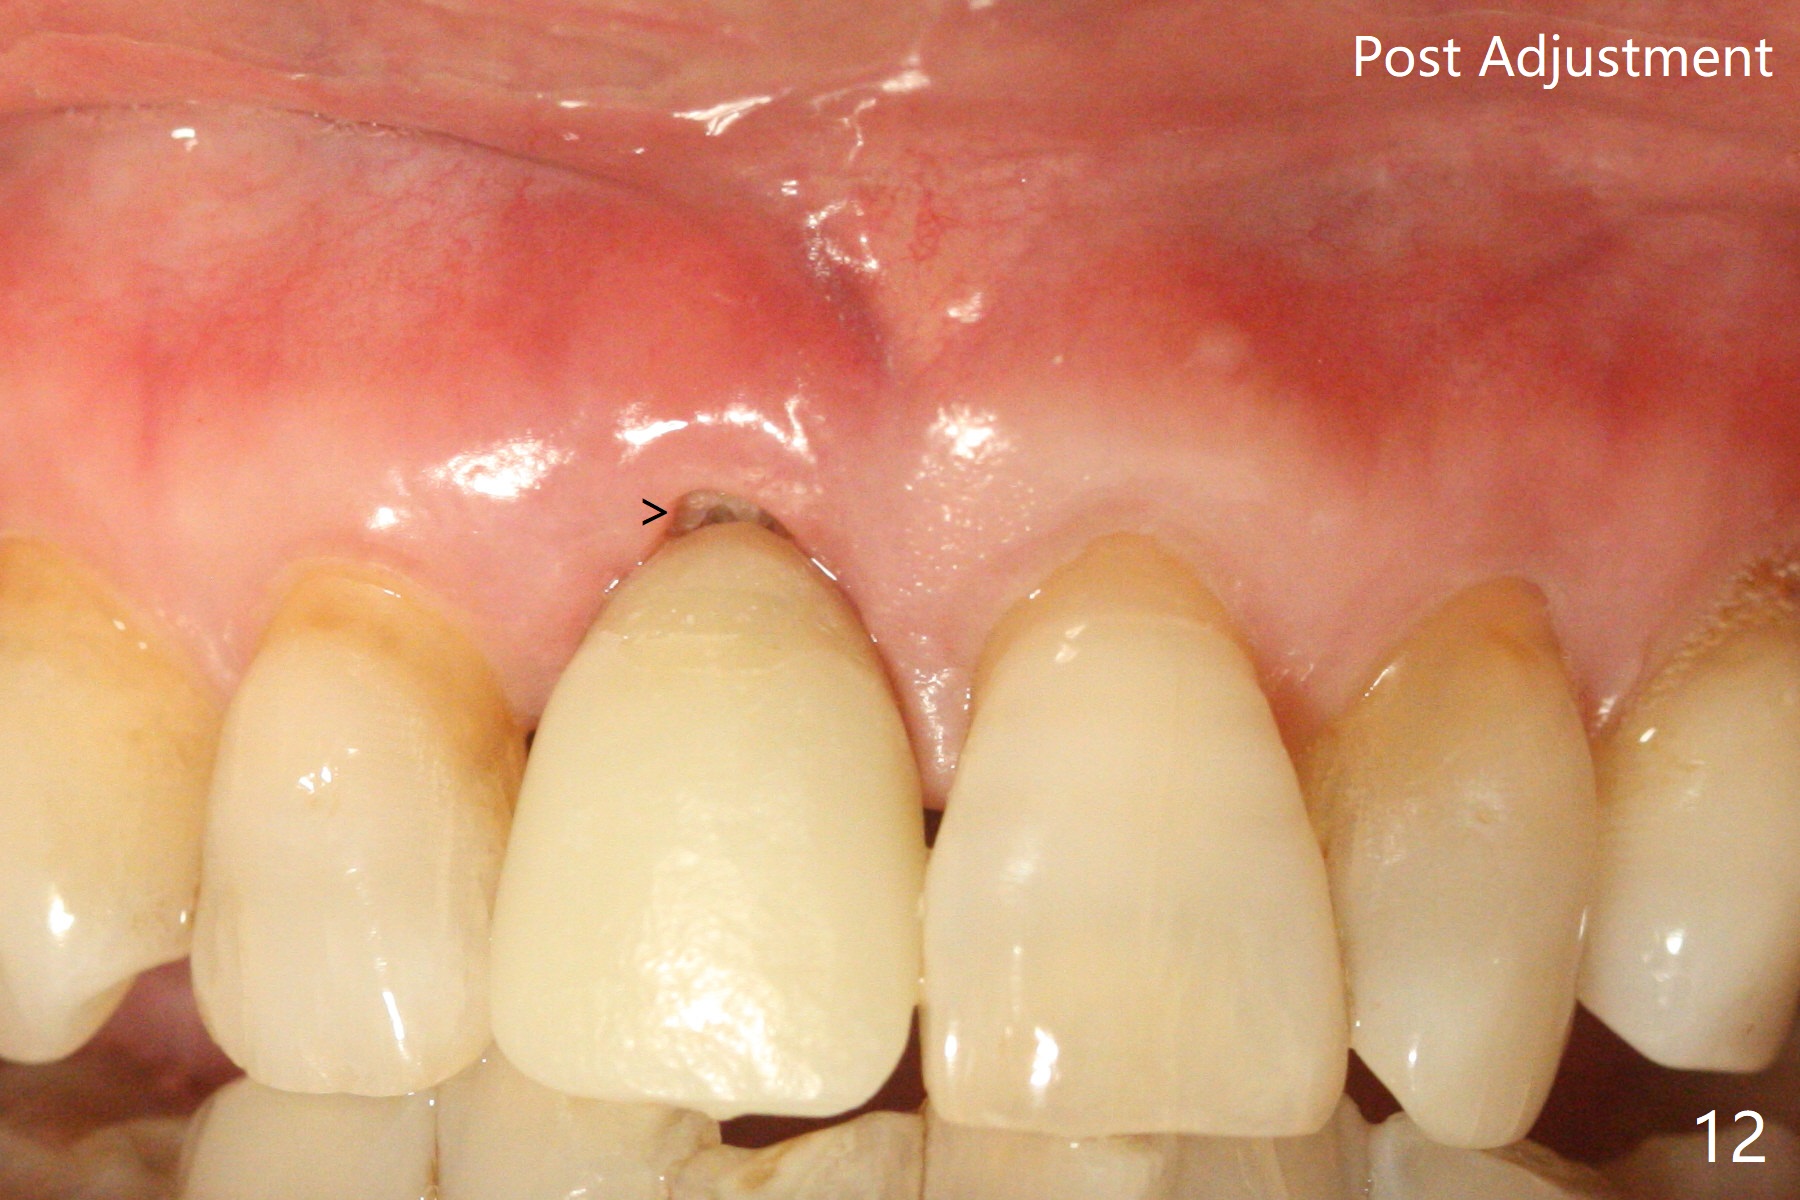

59岁女术前右下1,2切缘磨短后,右上1颊侧移位得到纠正(图一(咬合创伤))。拔牙后证实颊侧骨板缺失,钻洞始于腭侧(图二),当1.5毫米钻头感觉刚穿破鼻底时,置入2.5x14(4)毫米一段式植体,好像进入鼻腔,但是扭力<10Ncm(图三)。把一张PRF膜放入牙槽窝,一端紧贴颊侧牙龈腭侧,另一端放置颊侧牙龈颊侧(图四),然后开始用粘性骨粉(图五,七:*(100%皮质骨))充填颊侧间隙。后者填满时(图五:*),将外面一端PRF翻转覆盖牙槽窝开口,并插入基台固定(图六),最后插入龈下,用临时牙冠固定(图八(T),九(*:PRF))。术后九天牙龈退缩(图十:^),临时牙冠突出(*),后者龈缘和切缘进行调整,缩短(图十一,十二),少许骨粉暴露(图十二:>),十四天后牙龈往下生长,好像形成角化龈(图十三:*)。